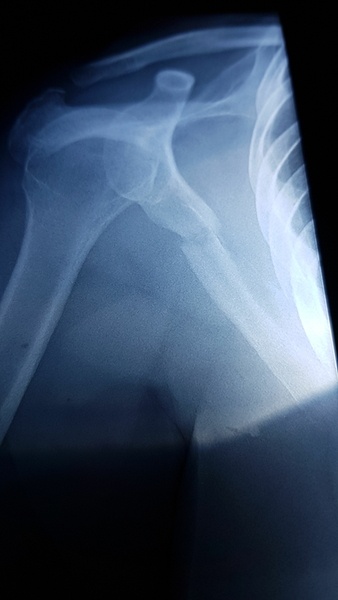

La fracture, c'est l'omoplate droite et 2 côtes en prime. J'apprends à utiliser ma main gauche et je visionne les vidéos de Boris et d'Olivier en attendant de pouvoir regagner l'atelier.

(La vache, c'est quand même violent quand je vois la radio... tu as dû douiller !)